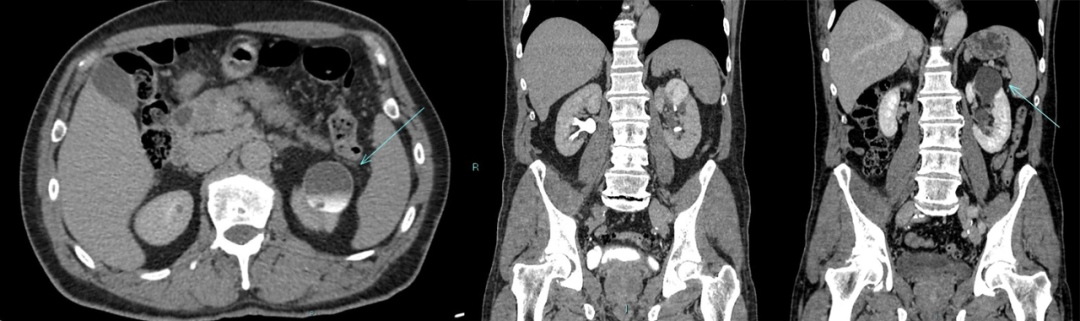

1、静脉尿路造影:表现为肾实质内圆形、边缘光滑的对比剂充盈区,有时可见与肾盏相通的细长管道。合并结石表现为囊腔内高密度影。

红色箭头所指为憩室,黄色箭头所指为肾盏。

2、肾盏憩室主要表现为:肾内囊性占位,平扫时囊性灶与肾盏分界不清,增强后造影剂进入囊肿(主要在延迟期造影剂进入憩室内);有时囊肿内可以看到结石或者钙乳样沉积物;肾盏憩室病灶主要偏向外周生长。